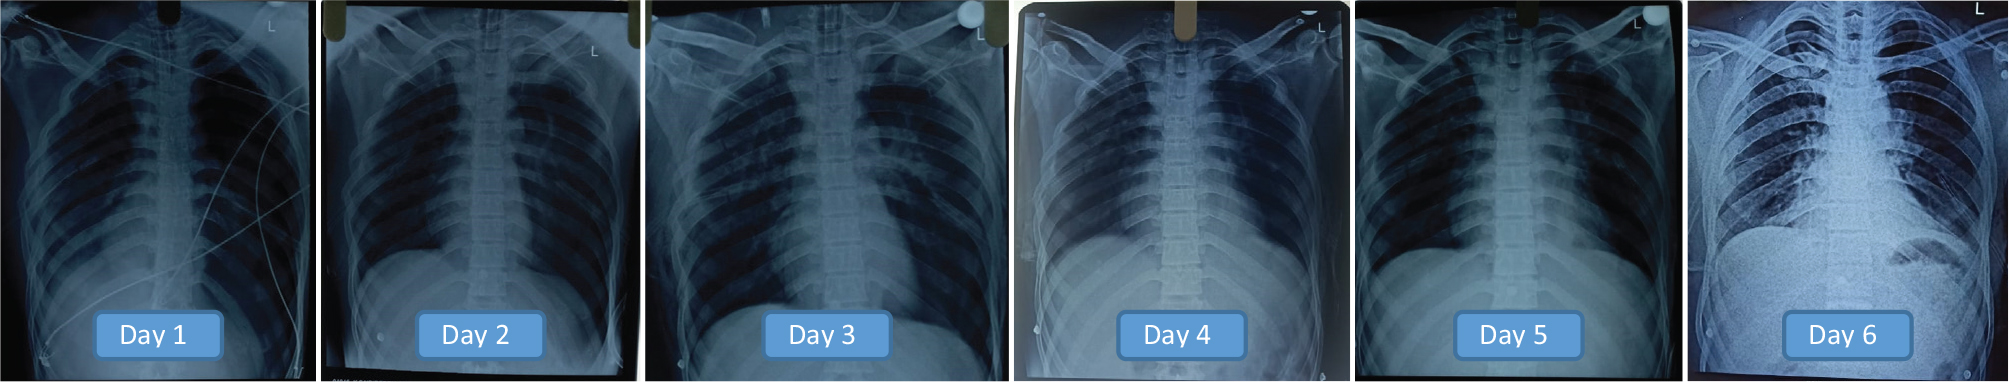

The cardiac surgeon recommended replacing the intercostal tube drainage bag with a bottle and coupled to 30-cm H2O-negative suction. The tele-ICU team reviewed images and recommended daily chest X-rays. And the drain output gradually decreased in tandem with good lung expansion. The tele-ICU team evaluated the patient’s spontaneous breathing, carefully examining the tidal volumes, calculating the rapid shallow breathing index (RSBI), and advising the peripheral center team when to remove the patient from the ventilator. The ability to view the patient and the ventilator at the same time with the help of the PTZ cameras helped the intensivist accurately analyze the spontaneous breathing trial and RSBI.

The patient’s breathing gradually improved. On Day 5, the patient was extubated following 4 days of mechanical ventilation after ensuring good lung expansion and evaluating spontaneous breathing using the rapid shallow breathing index (Figure 6). A repeat HRCT confirmed that lung expansion was adequate. Oxygen was gradually tapered and then stopped, and the patient was discharged after 10 days.

Fig 6

Fig. 6. The patient’s X-rays (day 1 through day 6) reveal gradual improvement. On Day 5, the patient was extubated following 4 days of mechanical ventilation.